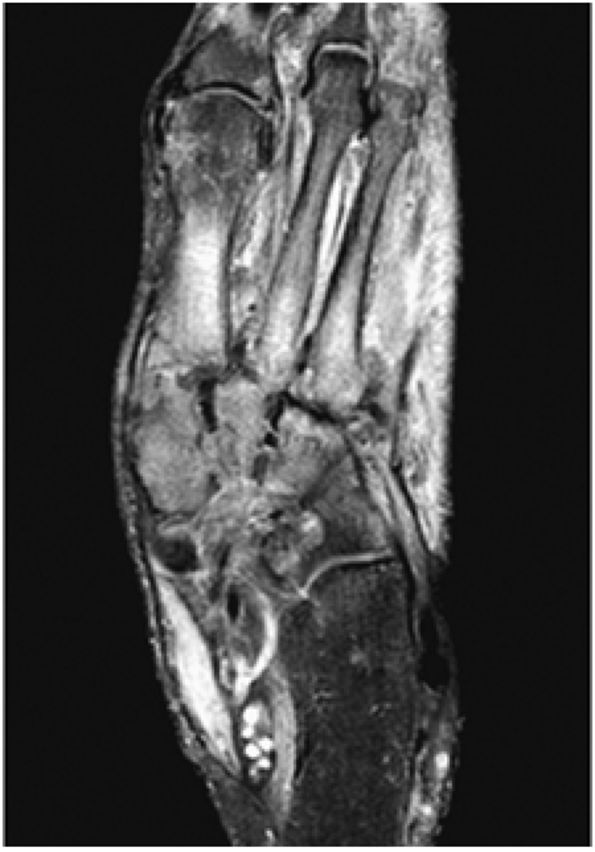

FIGURE 5.27 ● Axial anatomy of the ankle and foot. (A) The flexor digitorum longus, flexor hallucis longus, peroneus brevis, soleus, and extensor digitorum muscles are examined at this level for strain, tears, or fatty atrophy that may suggest denervation. (B) The tibialis anterior, extensor hallucis longus, and extensor digitorum longus tendons are examined on every ankle MR examination. Extensor tendon pathology is frequently overlooked if these tendons are not included as part of the ankle checklist. (C) Tears and sprains of the anterior syndesmotic ligament are a frequent cause of persistent ankle pain following ankle sprain. The syndesmotic ligaments are thick, tough ligaments that are important ankle stabilizers, and delayed diagnosis of syndesmotic tears may result in significant degenerative arthrosis at the tibiotalar joint due to the resulting ankle instability. The syndesmotic ligaments course obliquely inferiorly from the tibia to the fibula and are not usually visualized in their entirety on a single axial image; rather, their course is followed on at least two or three successive axial images. (D) The peripheral margin of the peroneal tendons and tibialis posterior tendon should normally never extend beyond the peripheral margins of the lateral and medial malleoli, respectively. Tendon subluxation around the posterior corner of either malleolus is indicative of a tear of the overlying flexor retinaculum (medially) or peroneal retinaculum (laterally). When the retinacula are torn, the tendon is free to intermittently sublux or dislocate, leading to tendon degeneration, pain, and tendon dysfunction. (E) Suspected osteochondral lesions of the talar dome are visualized and further characterized on axial images through the top of the talar dome. (F) The peroneus brevis tendon may normally appear somewhat flattened. However, as the tendon degenerates, it becomes U-shaped and drapes around the anterior aspect of the peroneus longus and becomes impinged between the peroneus longus tendon and the lateral malleolus. With further degeneration, the peroneus brevis may split or completely rupture. (G) Evidence of anterior talofibular ligament injury is visualized on the majority of MR ankle examinations and appears as thickening, intermediate signal with ill-defined fibers, or attenuation of the ligament. This is commonly asymptomatic. (H) Because the flexor hallucis longus tendon sheath communicates with the tibiotalar joint, fluid may normally be present within the tendon sheath in proportion to the amount of fluid in the tibiotalar joint. If there is fluid within the tendon sheath out of proportion to that seen in the tibiotalar joint, tenosynovitis is most likely present. The finding of flexor hallucis longus tenosynovitis should prompt a search for an os trigonum, as impingement of the flexor hallucis longus tendon between an os trigonum and the posterior tibial plafond is a common cause for FHL tenosynovitis. (I) The calcaneofibular ligament (CFL) passes anterior and medial to the peroneal tendons. On the image at which the CFL passes directly medial to the peroneus brevis tendon, the appearance of the peroneus brevis and the CFL side by side is occasionally mistaken for a split peroneus brevis tendon. (J) Dilated posterior tibial veins within the tarsal tunnel occasionally compresses the tibial nerve. In the setting of clinical suspicion for tarsal tunnel syndrome or if there is evidence of muscle denervation on MR images, the size of the posterior tibial veins should be described. (K) The spring ligament is identified at this axial image location, extending from the anteromedial calcaneus to the posteromedial navicular. Tears of the spring ligament may result in medial instability and hindfoot valgus. (L) The posterior tibialis tendon (PTT) may normally become thickened and fan-like as it passes posterior to its navicular insertion (prior to also inserting on the cuneiforms and the base of the second through fourth metatarsals). In the absence of other findings, the thickening of the PTT at this level should not be mistaken for focal tendinosis. (M) On inferior images through the ankle, Lisfranc's ligament is occasionally included in the FOV. Lisfranc's ligament extends from the medial cuneiform to the base of the second metatarsal. If Lisfranc's ligament is included in the FOV, the status of the ligament should be described, as undiagnosed Lisfranc ligament tears can lead to debilitating midfoot arthrosis. (N) As the medial and lateral tendons turn from their vertical course to a horizontal course along the plantar aspect of the foot, the tendons may demonstrate a magic-angle artifact, causing the tendons to appear gray on short-TE images, mimicking tendinosis. Correlation with images using longer TE values is advised in such situations.

arthrosis at the tarsal-metatarsal joints in particular should prompt a careful search for Lisfranc fracture—dislocations in the axial plane.